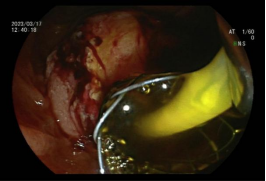

3.早期消化道肿瘤ESD技术

内镜下粘膜剥离术(ESD),具有超级微创、安全性高、住院时间短及费用低等优势,治疗早期胃癌、食管癌、大肠癌等病变,5年生存率超90%。

直肠巨大绒毛状腺瘤 内镜下粘膜剥离过程

粘膜剥离术后创面 剥离的巨大腺瘤